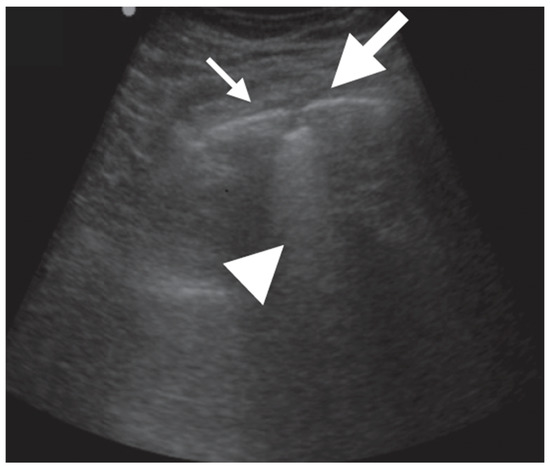

- Rea, G.; Sperandeo, M.; Lieto, R.; Bocchino, M.; Quarato, C.M.I.; Feragalli, B.; Valente, T.; Scioscia, G.; Giuffreda, E.; Foschino Barbaro, M.P.; et al. Chest Imaging in the Diagnosis and Management of Pulmonary Tuberculosis: The Complementary Role of Thoracic Ultrasound. Front. Med. 2021, 8, 753821. [Google Scholar] [CrossRef]

- Giannelli, F.; Cozzi, D.; Cavigli, E.; Campolmi, I.; Rinaldi, F.; Giachè, S.; Rogasi, P.G.; Miele, V.; Bartolucci, M. Lung ultrasound (LUS) in pulmonary tuberculosis: Correlation with chest CT and X-ray findings. J. Ultrasound 2022, 25, 625–634. [Google Scholar] [CrossRef]